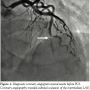

Revascularization was considered appropriate. The patient was hospitalized and PCI was performed the following day after hydration. Angiography by guide catheter was not performed. By referring to the diagnostic angiography, a Runthrough® guidewire (Terumo Medical, Somerset, New Jersey) was advanced into the diagonal artery and bifurcated immediately before the lesion. Following this step, by an Eliminate® aspiration catheter (Terumo Europe, Leuven, Belgium), selective coronary angiography was performed from the proximal part of the lesion using a contrast volume of 2.5 ml (Figure 2). Subsequently, a second Runthrough® guidewire was advanced through the lesion in the LAD using a Finecross® microcatheter (Terumo Medical). Passage of the guidewire through the true lumen could be confirmed via the sensation conveyed to the fingertips, as well as by the observation that the wire easily passed through the side branch distal to the lesion. The lesion was dilated using a 2.25 × 10 mm Ryujin® balloon catheter (Terumo Europe), and then, intravascular ultrasonography (IVUS) was performed to mark the optimal location (Figure 3). After a 3.0 × 18 mm Xience V stent (Abbott, Abbott Park, Illinois) was placed, we confirmed by IVUS that the artery was free from dissection and hematoma. After re-crossing to the diagonal artery and LAD using the Runthrough® guidewires (Terumo Medical), we performed simultaneous dilation with a 2.25 × 10 mm Ryujin® (Terumo Europe) and a 3.5 × 10 mm bpi® balloon catheter (Kaneka, Osaka, Japan). IVUS confirmed satisfactory dilatation of the stent, no malapposition, no dissection or hematoma at both edges, and no damage of the left main trunk caused by the guide catheter. Finally, selective coronary angiography was performed using the Eliminate® aspiration catheter (Terumo Medical) with a contrast volume of 2.5 ml, and satisfactory result was confirmed (Figure 4). The total amount of contrast medium during the procedure was 5 ml.

In the present case, several measures were taken to minimize the contrast volume. Preprocedure coronary angiography was not performed and selective coronary angiograms using an aspiration catheter and IVUS images were completely utilized. An aspiration catheter, which does not require the removal of the guidewire before the selective angiogram, offers sufficient luminal space to obtain satisfactory angiograms and may be the optimal device for the present purpose. We could obtain satisfactory images to assess the lesion using an aspiration catheter with a contrast volume as small as 2.5 ml without strong resistance. PCI using a smaller contrast volume could be performed safely taking these measures.